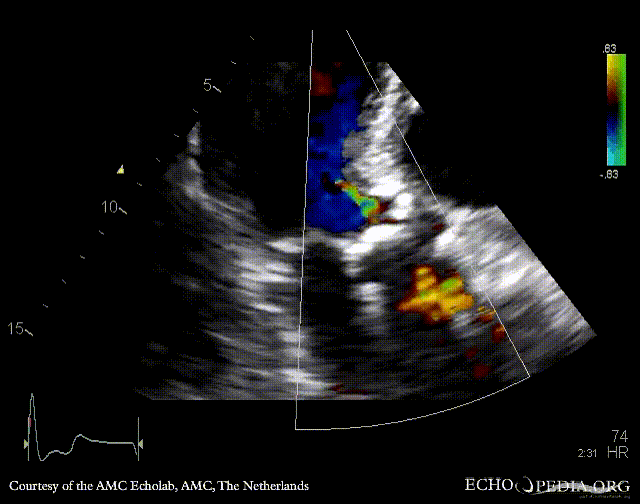

| PSAX: stenosis of aortic valve | PLAX with Color Doppler: high velocity transaortic flow, mild aortic regurgitation |